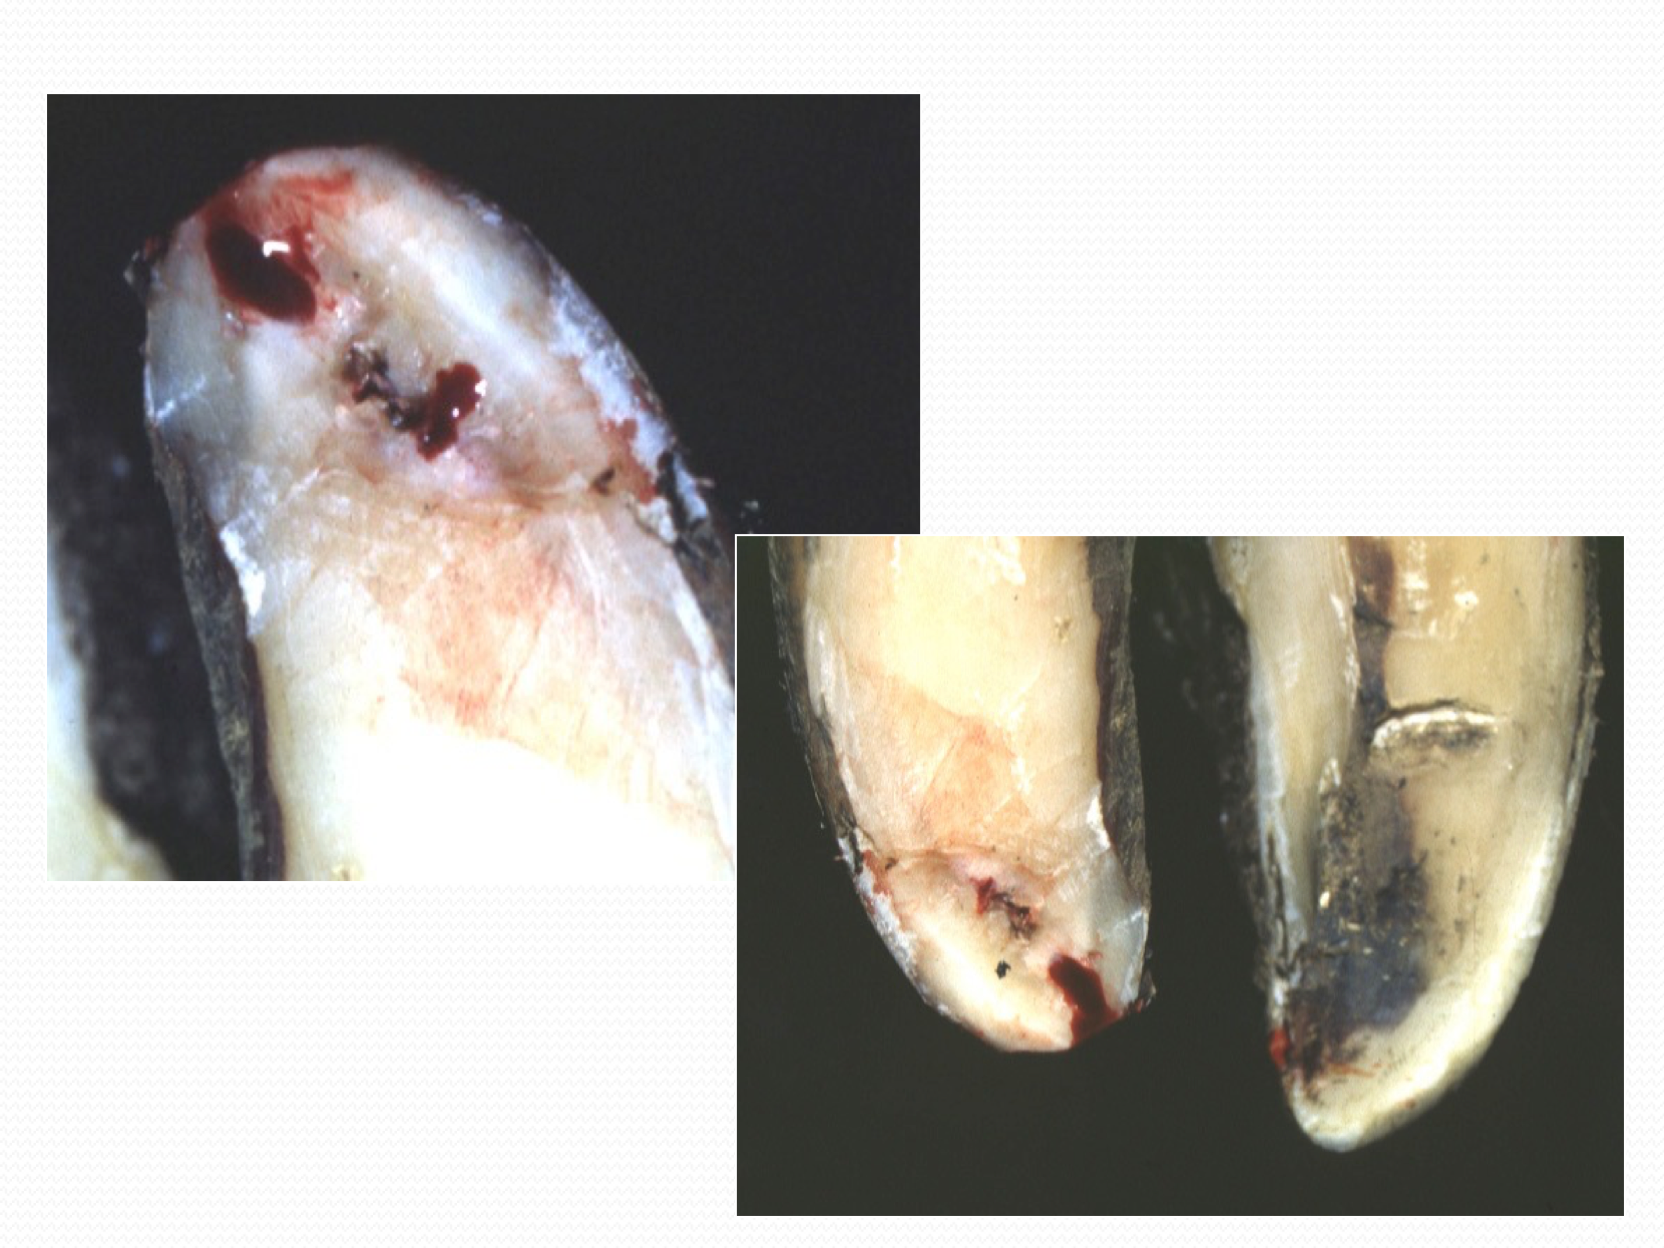

Deep Digital Sepsis

What causes it?

- Extremely lame cow, non-weight bearing with swelling usually off center and encircling a claw (usually the outer claw of the rear foot)

- Caused by complication of sole ulcers, white line abscesses, sole puncture, and foot rot where infection spreads to the deeper tissues of the claw including the digital cushion, distal interphalangeal joint, pedal bone and flexor tendon sheaths

How do we treat it?

- Treatment should be implemented only by a veterinarian and involves drainage of the infected area and ankylosis (fusion) of the distal interphalangeal joint

- Most cows should be euthanased with this condition on animal welfare grounds

- Severely lame cows should not be shipped for slaughter

How do we prevent it?

- Cows with deep digital sepsis represent a complete failure of the herd lameness prevention and identification program

- The presence of such a cow in the herd should trigger a full review of all lameness related procedures on the farm